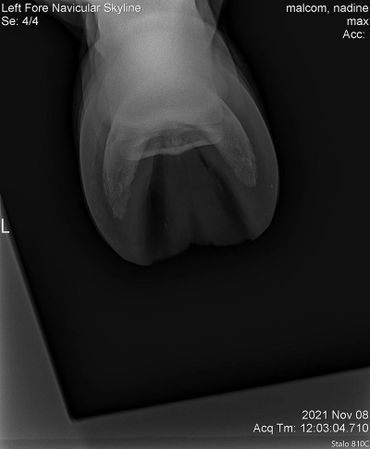

Due to an old injury Max was never sound on his front left. However, with Equioxx we have been able to keep him comfortable. He started going more lame on that foot so we had Dr. Johnson take a look at it. We did a nerve block and some x-rays to see what is going on. There are no significant changes to see so in the future on bad days we will just give him some banamine as well.